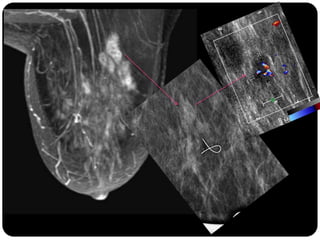

Paciente femenina de 66 años con historia clínica de 1er gesta antes de los 30 años y antecedentes de lactancia positiva, presenta una lesión palpable en la mama derecha. Los estudios radiológicos indican un diagnóstico de bi-rads 5, con biopsias revelando adenocarcinoma lobulillar infiltrante en la glándula mamaria derecha y adenocarcinoma ductal in situ en la izquierda. El caso fue evaluado por las doctoras Jacqueline Preciado Vargas y Beatriz E. González Ulloa.